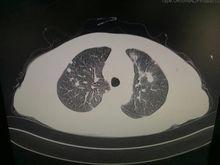

肺鈣化灶CT表現(圖2):兩肺瀰漫性粟粒樣影